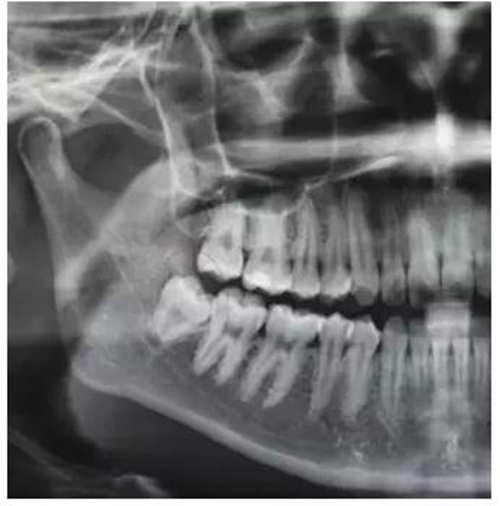

圖2.全景片局部放大影像:48融合根、牙根未發(fā)育完成,牙周膜清晰。

(5)該病例牙根呈錐形、牙根未發(fā)育完成、遠(yuǎn)中牙囊影比較明顯,故不用分牙,直接用挺拔除。